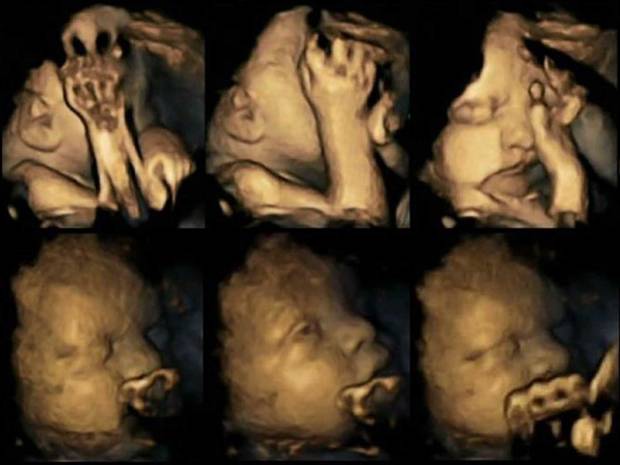

Ovi snimci 4D ultrazvuka vrlo verno prikazuju što pušenje čini vašem nerođenom detetu. Snimci su pokazali kako deca majki koje u trudnoći puše mnogo više dodiruju ručicama usta i lice nego bebe trudnica koje ne puše.

Stručnjaci tvrde kako pušenje tokom trudnoće može bitno odložiti i usporiti razvoj bebinog centralnog nervnog sistema. Sada naučnici veruju da najasnije mogu prikazati posledice pušenja na bebu u materici i pritom koriste slike s ultrazvuka kako bi podstakli trudnice na prestanak pušenja.

U sklopu istraživanja koriste se 4D snimci koje mogu snimiti na hiljade sitnih pokreta u materici i mnogo su verniji prikaz jer klasični 3D ultrazvuk sada prikazuje i pokret. smrti, SIDS-a.

Istraživanje je pratilo 20 majki koje su bile u Univerzitetskoj bolnici James Cook u Middlesbroughu, od kojih su četiri pušile u proseku 14 cigareta dnevno. Nakon proučavanja u 24. , 28. , 32. i 36. nedelji dokazano je kako bebe pušačica mnogo više dodiruju lice i rade više pokreta usnama nego što je to inače uobičajeno kod beba iste starosti.